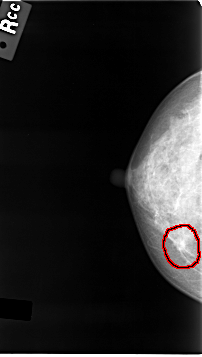

C_0015_1.RIGHT_CC

RIGHT_CC LINES 4640 PIXELS_PER_LINE 2616 BITS_PER_PIXEL 12 RESOLUTION 50 OVERLAY

FILE: C_0015_1.RIGHT_CC.OVERLAY

TOTAL_ABNORMALITIES 1

ABNORMALITY 1

LESION_TYPE MASS SHAPE IRREGULAR MARGINS SPICULATED

ASSESSMENT 5

SUBTLETY 5

PATHOLOGY MALIGNANT

TOTAL_OUTLINES 1

BOUNDARY